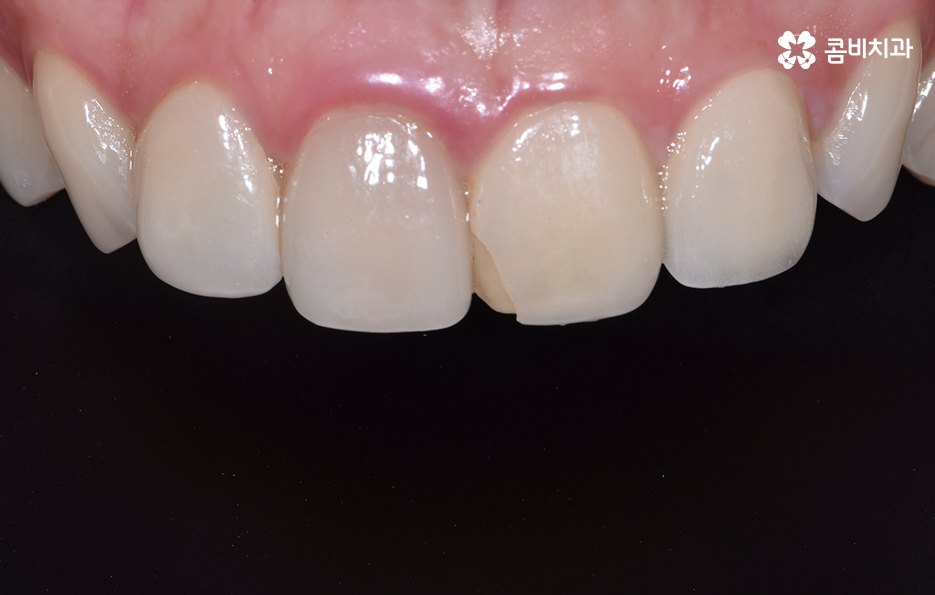

위 환자분의 경우 기존에 타 치과에서 치료받으셨던

라미네이트가 깨져서 내원하셨습니다.

앞니 충치치료 후 레진이나 라미네이트가 깨지는 사례가

종종 있는데 치료 후에는 평상시 생활 습관에 있어서

주의가 필요하며 이 악물기와 같은 습관이 있으신 경우

검사를 통해 개선 방안과 원인을 찾아보는 게 좋습니다.